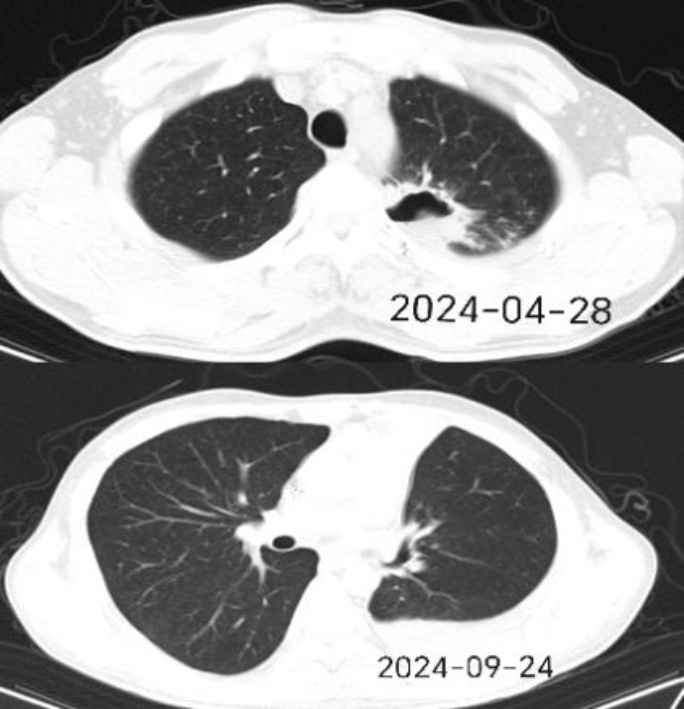

胸部CT示25例患者有肺部炎症,其中6例患者具有典型的反晕征(图1),1例患者表现为多发类圆形软组织密度影;所有患者都常规进行了真菌G、曲霉菌GM试验,结果显示,2例患者2项指标均为阳性,3例仅GM试验呈阳性,另有2例仅G试验结果为阳性。

Figure 1. Representative chest CT images showing the reversed halo sign in selected patients before and after treatment

1. 代表性的胸部CT图像显示了部分患者治疗前后的反晕征。

本研究采用Kaplan-Meier法及Log-rank检验对预后相关因素进行了单因素生存分析。结果显示,抗毛霉药物治疗的启动时机表现出与患者生存率的显著相关性。早期治疗组的累积生存率显著优于延迟治疗组(Log-rank P = 0.015,图4)。具体而言,早期治疗组(治疗启动 ≤ 5 d)的中位生存期未达到,提示,该组超过50%的患者在随访结束时依然存活;相比之下,延迟治疗组(治疗启动 > 5 d)的中位生存期仅为61.0 d (95% CI: 32.9~89.1)。这一显著的生存获益表明,在出现疑似症状或影像学征象(如反晕征)后5 d内启动治疗可能改善预后。其他潜在预后因素结果显示,原发病状态及既往真菌感染史在两组间的生存曲线差异未达到统计学显著性水平(Log-rank P > 0.05)。考虑到本研究样本量(N = 26)及观察到的死亡事件数(N = 9)相对有限,这一结果可能与统计效能不足有关,尚不能完全排除上述因素在更大样本队列中具有临床预后价值的可能性。

毛霉菌感染起病隐匿,早期临床表现缺乏特异性(主要为发热、咳嗽),确诊难度极大。影像学检查在早期识别中具有重要提示意义,本研究中有6例患者呈现典型的“反晕征”,部分患者伴有病灶周围大面积磨玻璃影,这与既往研究指出的影像学特征一致[7]。此外,鉴于毛霉菌易侵犯副鼻窦及血管的生物学特性[8],对于不明原因咯血(本组4例)或顽固性高热患者,应高度警惕并完善肺部、鼻窦CT排查。